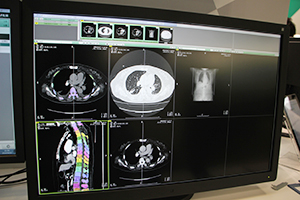

ITコーナーでは,3D画像解析システム「SYNAPSE VINCENT」の最新のバージョン4のソフトウエアを中心に展示した。泌尿器科領域での腎臓の腹腔鏡下手術シミュレーション,頭部の神経線維や血管などを表示した開頭手術シミュレーションなどのほか,モバイル端末への対応などをアピールした。そのほかSYNAPSEの新機能として,画像認識技術を使った骨ラベリング,肝臓がんに対応したSYNAPSE CaseMatchなどを紹介した。

SYNAPSE VINCENTの新しいソフトウエアを紹介。泌尿器科領域での腎臓の腹腔鏡下手術シミュレーション